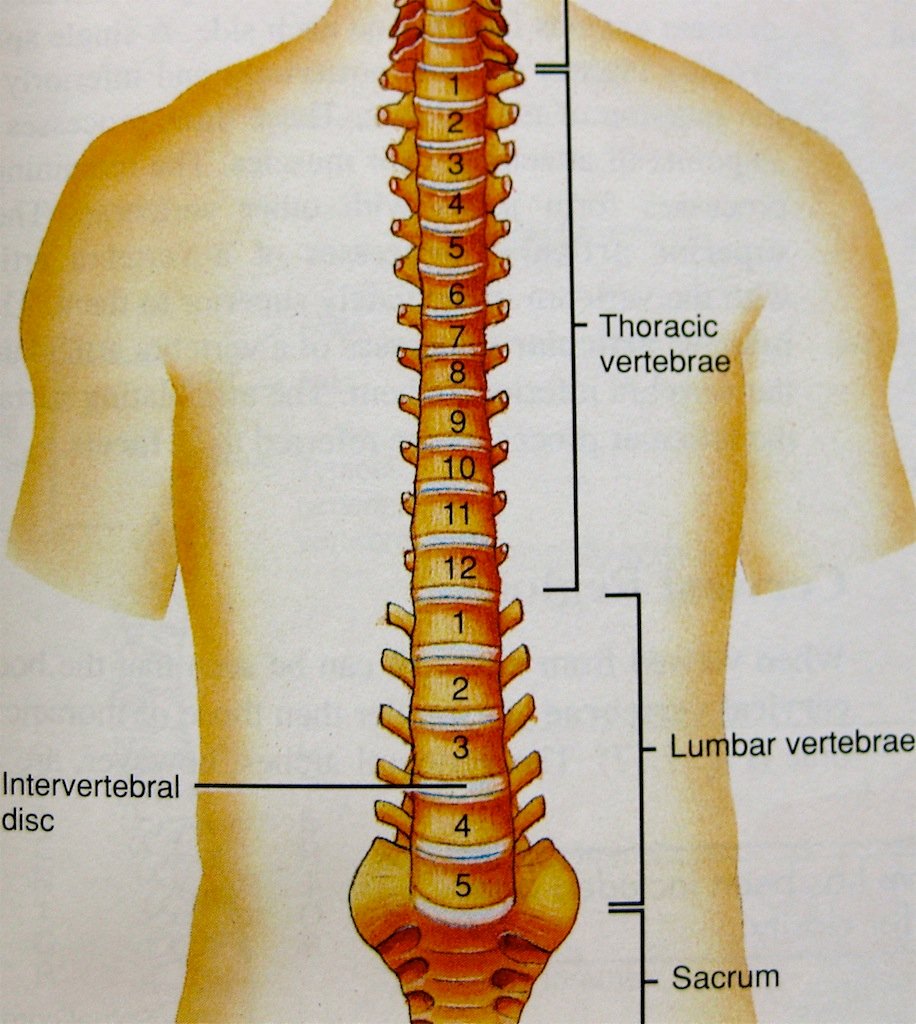

silikonsheet.blogg.se – Spine diagram

The number of intervertebral discs in the human spine class 11 biology CBSE

Anatomy of the Spine | Globus Medical

Information about spine and intervetebral disc anatomy – Dr David Oehme …

Anatomy of the Spine | Wessex Spinal Surgeon

Spine Anatomy and Back Pain – The Core Expert

Anatomy of the Lumbar Spine – TrialExhibits Inc.

Learn all about lumbar spine anatomy from a world-renowned Spine Expert …